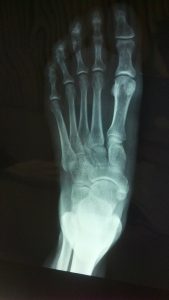

A foot fracture is a bone break in one of the bones of your foot. The most common types of foot fractures include toe fractures and metatarsal fractures. As described, a toe fracture is a break in the toes of your foot, while metatarsal fractures are breaks in the long bones that attach to the base of each toe.

If you suspect a foot fracture, contact your doctor for a thorough physical examination and proper diagnosis. Your doctor may order imaging tests to determine the precise location and severity of the fracture.